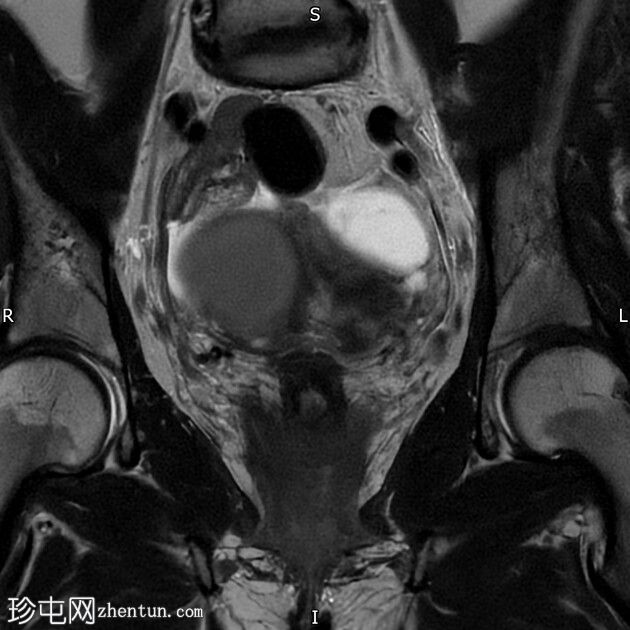

冠状位

T2加权像

右侧卵巢囊肿,T2加权像呈低信号,T1脂肪抑制像呈高信号,大小为6 x 5.2 cm,符合子宫内膜异位囊肿的影像学表现。

左侧卵巢囊肿,T2加权像呈低信号,T1脂肪抑制像呈高信号,符合子宫内膜异位囊肿的影像学表现。

双侧卵巢粘连于后道格拉斯窝,呈“接吻卵巢征”。

多发性子宫肌瘤。宫内放置宫内节育器。

结论:双侧卵巢子宫内膜异位囊肿。多发性子宫肌瘤。

本病例显示右侧卵巢子宫内膜异位症,左侧卵巢囊肿内含出血性物质,并可见“接吻卵巢征”,诊断为卵巢子宫内膜异位囊肿伴可能粘连/深部盆腔子宫内膜异位症。

此外,还存在子宫肌瘤。